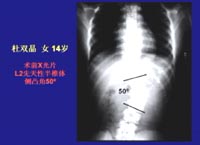

王岩:术前从大体的外观就可以看到双肩不等高,从后看可以看到脊柱畸形呈S状,如图患者杜双晶术前X光片先天性半椎体侧凸角50度。

张永刚:如图正常人无论从前面看还是从后面看,特别是从后面可以很清楚看到脊柱的轮廓,正常情况下从后面看脊柱都是笔直的,但是患者却出现了向一侧弯曲的情况,临床上通常把这种情况叫做脊柱侧凸。杜双晶的情况从临床上看并不是很严重的,但也是应该引起广泛关注的一种情况。